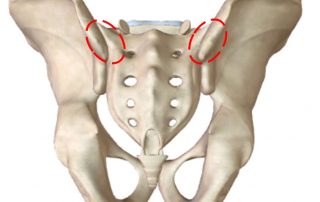

תלונה על כאבי גב תחתון היא נפוצה מאוד בקליניקה. לרוב, הכאב ממוקם לרוחב "חגורה" - כלומר משני צדי הגב; במרכז אבל "רחב" (מטופל מניח את כף היד על האיזור הכואב); או בצד אחד (גם אם המטופל אינו מודע לזה, בהרבה מקרים בהם הוא מתלונן על כאב גב מרכזי - הוא בעצם דומיננטי יותר בצד [...]